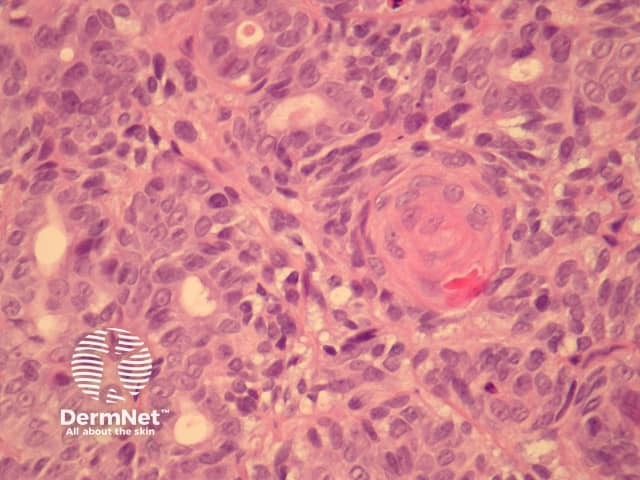

In aggressive digital papillary adenocarcinoma, sections show a dermally based tumour, which may connect with the overlying epidermis (figure 1). The tumour may be cystic, papillary, ductal or solid. The example illustrated here has a predominantly solid and ductal morphology with only focal areas of papillary formation. The cells are basaloid, show enlarged atypical nuclei, large nucleoli and increased mitoses (figures 1-6). Squamous metaplasia within the tumour may be seen (figure 5).

Figure 3